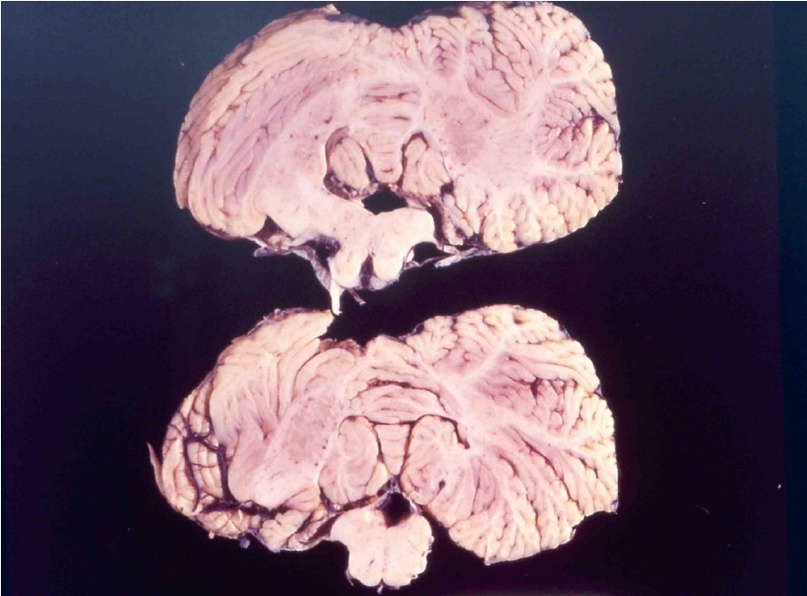

При болезни куру патологические изменения можно наблюдать только в центральной нервной системе. Обычно они выражаются в формировании типичной губчатой энцефалопатии. В коре, подкорковых ядрах, подбугорной области и в мозжечке наблюдается вакуолизация дендритов, аксонов и тел нейронов. Вакуолизация становится настолько выраженной, что серое вещество коры большого мозга приобретает вид губки, в результате чего такое состояние обозначают как status spongiosus. Методом электронной микроскопии было выяснено, что вакуоли окружены фрагментами таких же пролиферирующих мембран. Характерный патогистологический признак при куру – выпадение нейронов.

головного мозга

страдавшего от болезни

взрослого мужчины,

который впоследствии

погиб от куру

Изменения нейронов сочетаются с гипертрофией и размножением астроцитов. При куру у человека патогистологические изменения наиболее выражены в мозжечке: появляются аморфные ШИК-положительные бляшки, содержащие амилоид, уменьшается количество грушевидных нейронов (клеток Пуркинье). Вместе с тем, при куру не удаётся обнаружить воспалительной реакции, столь характерной для многих заболеваний ЦНС, или таких характерных признаков вирусной инфекции, как образование телец включений или глиальных узлов.

Характерные для куру изменения ЦНС обнаруживаются ещё до появления клинических симптомов заболевания, что сопровождается снижением общего содержания ганглиозидов в сером веществе головного мозга на 40%. Однако сам прион не удаётся обнаружить ни в крови, ни в сыворотке, ни в моче, ни в спинномозговой жидкости. В молоке, ткани плаценты и амниотической жидкости у людей или экспериментально заражённых животных прион также не обнаруживается.